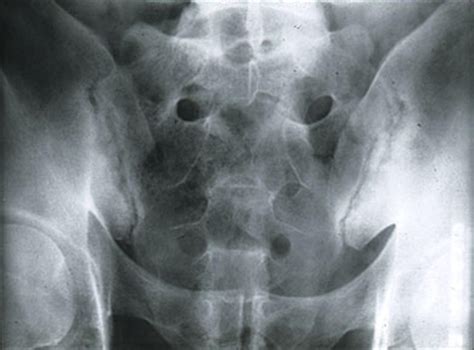

Anatomy of the human pelvis and spine

The sacroiliac joints are two small, powerful joints located on either side of the sacrum, the triangular bone at the base of your spine. These joints act as shock absorbers, transferring weight from your upper body to your lower extremities while providing stability. Unlike other joints in the body that require extensive range of motion, the SI joints are designed for limited movement. When this delicate balance is disrupted, inflammation occurs, leading to the hallmark Sacroiliac Joint Dysfunction symptoms that many patients struggle to describe to their doctors.